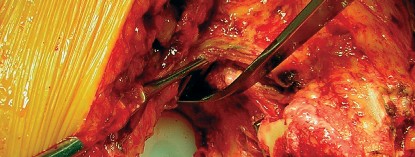

جراحة استبدال مفصل الورك الكلي (Total Hip Replacement - THR)

تتضمن هذه الجراحة استبدال الأجزاء التالفة من مفصل الورك بمكونات صناعية مصنوعة من المعدن، البلاستيك عالي الجودة (البولي إيثيلين)، أو السيراميك. الهدف هو تخفيف الألم واستعادة وظيفة المفصل.